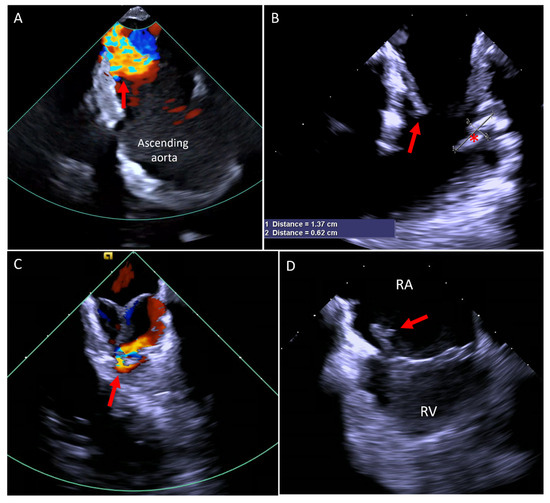

5.1. Paravalve Leak (PVL) Occlusion

- Alkhouli, M.; Sarraf, M.; Maor, E.; Sanon, S.; Cabalka, A.; Eleid, M.F.; Hagler, D.J.; Pollak, P.; Reeder, G.; Rihal, C.S. Techniques and Outcomes of Percutaneous Aortic Paravalvular Leak Closure. JACC Cardiovasc. Interv. 2016, 9, 2416–2426. [Google Scholar] [CrossRef]